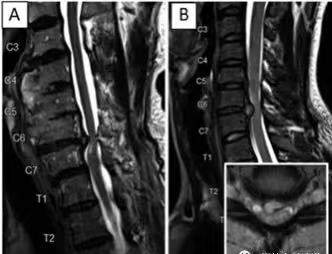

7.辅助检查:⑴颈部MRI是主要检查手段:可见脊髓或神经根受压,受压脊髓内高信号改变,横断面上见脊髓前角内局限的高信号,提示脊髓前角缺血性囊性空洞。⑵电生理检查:有利于进一步明确病变神经根和鉴别诊断,用于排除肌萎缩性侧索硬化症(ALS)。